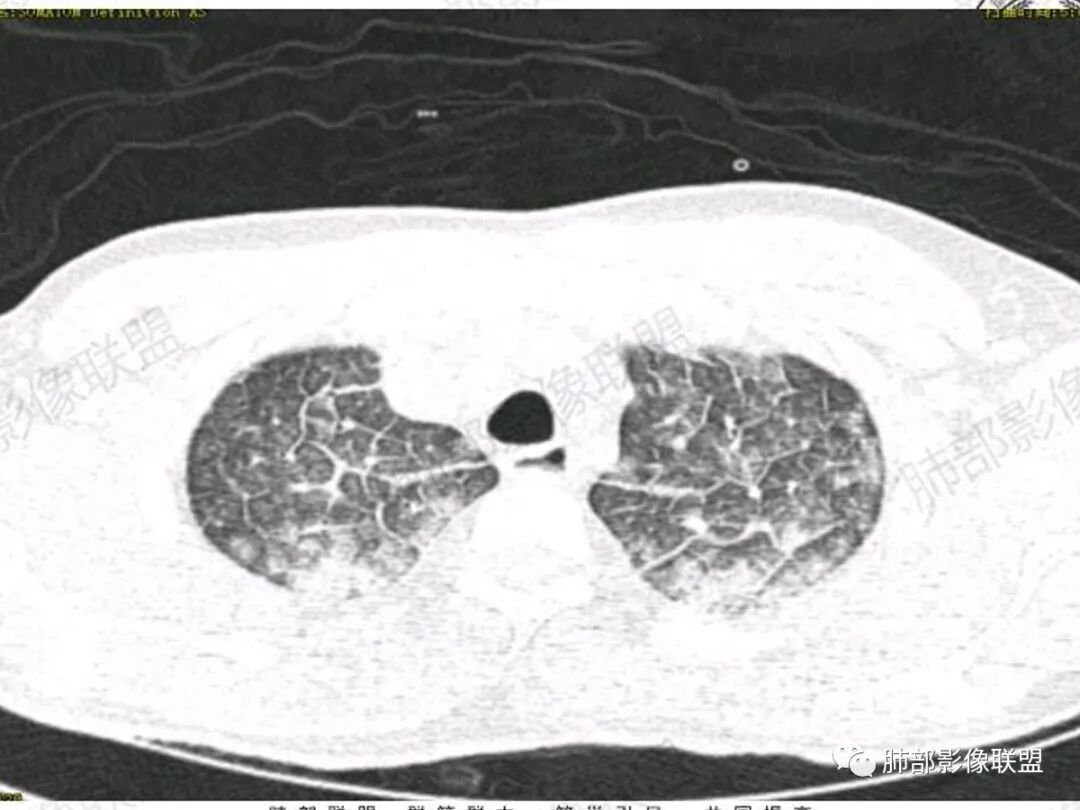

双肺上叶,下叶背段多发斑片状实变影,以胸膜下分布为主,部分重力作用,以背侧为主,部分小叶间质增厚,部分周围伴有散在磨玻璃影,边界欠清,临床急性病程,血象增及PCT明显增高,意识模糊,考虑:吸入性肺炎?鉴别:AHP?CEP?PCP

37岁男性 气促 两肺对称分布磨玻璃及小叶间隔增厚,两肺上叶后段及下叶背段为著,有重力分布,下部密度较高,请结合病史排查肺水肿,理化性肺泡损伤

双肺叶透亮度对称性减低,呈磨砂状,小叶间隔规则增厚,上叶为甚,左右肺叶中轴间质增厚(示淋巴回流障碍),双肺叶弥散磨GGO征,以肺腺泡分布,双肺上,下叶融合片状,有重力分布特点,心脏大,肺动脉干增粗,首选心源性肺水肿,但无胸腔积液。与急性肺损伤和ARDS鉴别

影像:两肺上叶小叶间隔增厚,斑片,腺泡结节,重力分布,下肺不累及

青年男性,气促7小时入院,意识模糊,白细胞及中性粒明显增高,PCT增高,CRP不高,心率快,体温正常,血压正常。胸部CT:双肺上叶小叶间隔光滑增厚,中轴间质增厚,弥漫性磨玻璃、多发斑片影,以上肺、背侧分布为主。影像表现考虑为肺水肿。病因:病史不支持肾功能衰竭、心源性、高原性肺水肿,无发热,似乎也不支持细菌、病毒、真菌等感染引起。吸入毒物?吸入水?

对称性小叶间隔增厚

高密度影重力趋势

病灶的分布以上肺为主

确实要考虑吸入,倾向于吸入的是气体类的可能,因为朝上走

结合病史,最终诊断是 “急性烟雾吸入性肺损伤”,影像学表现主要是肺水肿及弥漫性肺泡损伤改变,因为烟雾气体吸入肺内分布以上肺显著,因此影像学表现也是累及上肺更明显。损伤因素包括大量一氧化碳 二氧化碳 一氧化氮等燃烧产生的有毒气体,也有烟雾粉尘颗粒对气道黏膜的损伤。